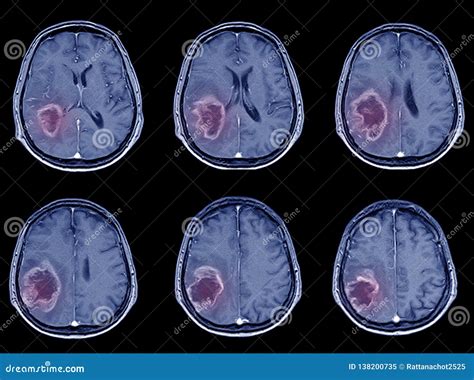

Early Signs of Ischemic Stroke on a CT Scan

In the early stages of an ischemic stroke , the CT scan might not show a lot of obvious changes. However, there are some subtle signs that experienced radiologists can spot. They look for the following signs:

• Loss of Grey-White Matter Differentiation: The brain is made up of grey matter and white matter, which have different densities. In the early stages of a stroke, the difference between these can become less clear, making it difficult to differentiate between them. This is often the first thing they notice.

• Hyperdense Artery Sign: Sometimes, the CT scan can show a blood clot as a very bright spot in an artery, known as the hyperdense artery sign. This is a telltale sign of a blood clot and helps to confirm the diagnosis.

• Subtle Swelling: The brain tissue may start to swell, and subtle changes in the density of the brain tissue. This can indicate that the brain is not getting enough blood.

Later Signs of Ischemic Stroke on a CT Scan

As time passes, the changes on the CT scan become more apparent. The following signs are usually visible later:

• Hypodensity: Areas of the brain that are damaged due to the lack of blood flow will start to appear darker on the CT scan. This is called hypodensity. It indicates that the brain tissue is dying.

• Mass Effect: As the brain swells, it can push on other structures, causing a mass effect.

• Infarct: This is a term for the area of dead tissue caused by the stroke. It can be seen as a clearly defined dark area on the scan.

Differentiating Ischemic vs. Hemorrhagic Stroke

One of the main goals of the CT scan is to differentiate between an ischemic stroke and a hemorrhagic stroke. A hemorrhagic stroke involves bleeding in the brain. On a CT scan, blood appears bright white. So, if the scan shows any bright white areas, it’s a sign of bleeding. If there’s no bleeding and the scan looks relatively normal (or shows the signs of ischemic stroke ), then it’s most likely an ischemic stroke . This distinction is super important because the treatments for each type of stroke are different.